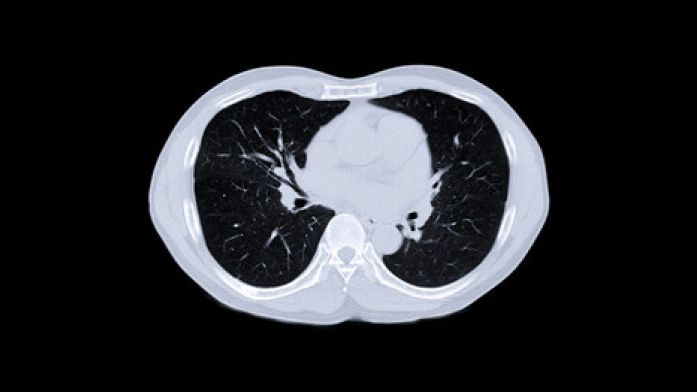

HRCT can provide information on the extent and severity of the disease. For more HRCT related information

For a RA-ILD risk score ≥7, perform high resolution chest CT directly